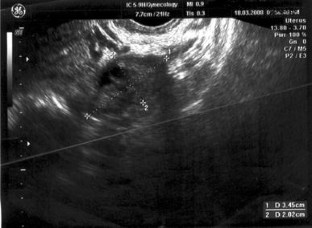

We report the fourth case of ovarian adenomyoma in a 45-year-old woman with an endometrial polyp. Transvaginal ultrasonography revealed a solitary endometrial polyp with an enlarged left ovary which appeared heterogenous with isoechoic and mildly hyperechoic pattern.

Fig. 1